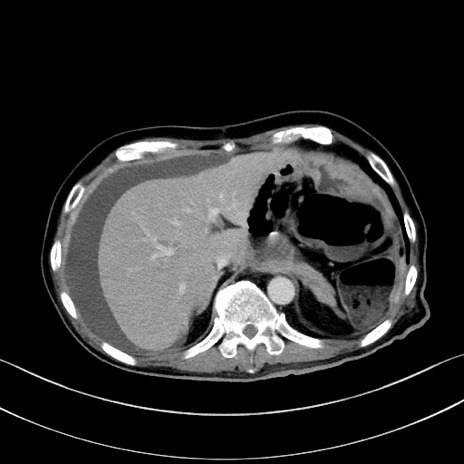

症例28(横断像)

【症例】60歳代男性

【主訴】嘔吐

【現病歴】胃癌にて胃全摘後。食思不振が悪化し、夜中に嘔吐することがある。

【既往歴】胃癌、胃全摘、脾摘、胆摘後

【データ】WBC 5900、CRP 10.56